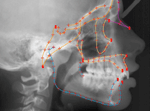

Computer survey. Halazonetis DJ, Abelson MN. Am J Orthod Dentofacial Orthop. 1999 Dec;116(6):699-701. doi: 10.1016/s0889-5406(99)70011-9. PMID: 10587607

Morphing and warping: Part II. Halazonetis DJ. Am J Orthod Dentofacial Orthop. 1999 Jun;115(6):706-8. doi: 10.1016/s0889-5406(99)70098-3. PMID: 10358255

Morphing and warping. Part I. Halazonetis DJ. Am J Orthod Dentofacial Orthop. 1999 Apr;115(4):466-77. doi: 10.1016/s0889-5406(99)70074-0. PMID: 10194292